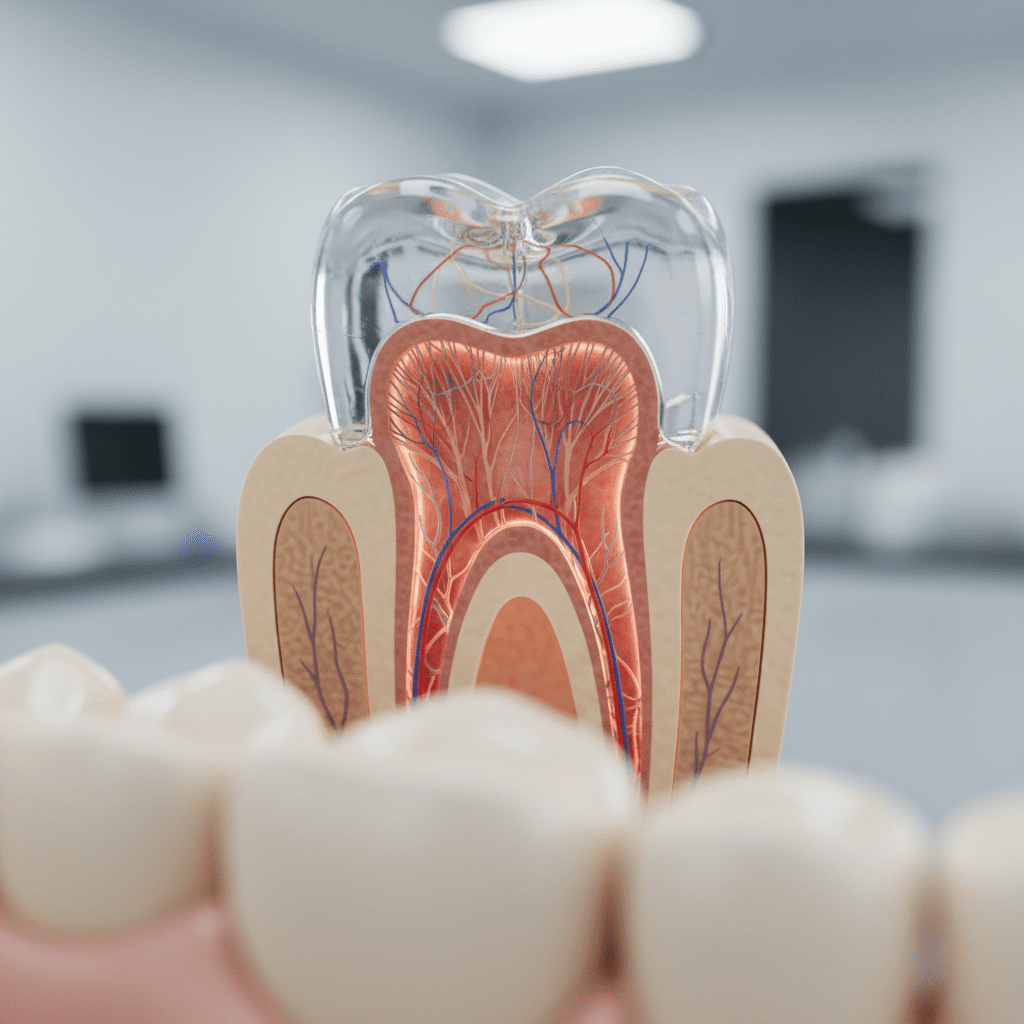

2. Dentina: O Coração do Dente

A dentina, localizada logo abaixo do esmalte, representa a maior parte da estrutura do dente. Essa camada é mais macia que o esmalte e contém túbulos microscópicos que se conectam à pulpa dental. A dentina é vital para a sensibilidade do dente, pois qualquer dano pode resultar em dor intensa.

Um aspecto interessante da dentina é que ela pode se regenerar em certa medida. Quando a dentina é danificada, o corpo pode produzir mais dentina em uma tentativa de proteger a polpa. Isso torna o cuidado preventivo ainda mais importante, pois danos prolongados podem levar a problemas mais graves, como infecções.

3. A Cavidade Pulpar: O Centro Nervoso

A cavidade pulpar é a parte interna do dente, onde se encontram os nervos e vasos sanguíneos. Essa estrutura é responsável pela nutrição do dente e pela percepção de dor. A polpa também desempenha um papel crucial na formação da dentina durante o desenvolvimento do dente.

Quando a pulpa é inflamada ou infectada, pode ser necessário realizar um tratamento de canal para salvar o dente. Os sinais de problemas na cavidade pulpar incluem dor intensa, inchaço e sensibilidade prolongada ao frio ou calor. A consulta ao dentista é essencial para diagnosticar e tratar adequadamente esses problemas.

5. Coroa, Colo e Raiz: A Estrutura Anatômica do Dente

Os dentes têm uma organização anatômica que pode ser dividida em três partes principais: coroa, colo e raiz.

Coroa

A coroa é a parte visível do dente, que é coberta pelo esmalte. É a seção responsável pela mastigação e pela estética do sorriso. A forma e o tamanho da coroa variam de acordo com o tipo de dente, seja incisivo, canino ou molar.

Raiz

A raiz é a parte do dente que está fixa no osso da mandíbula ou maxila. Ela é essencial para a estabilidade do dente e é coberta por cemento. A profundidade da raiz pode variar entre os diferentes tipos de dentes e é uma característica importante a ser considerada durante procedimentos odontológicos.